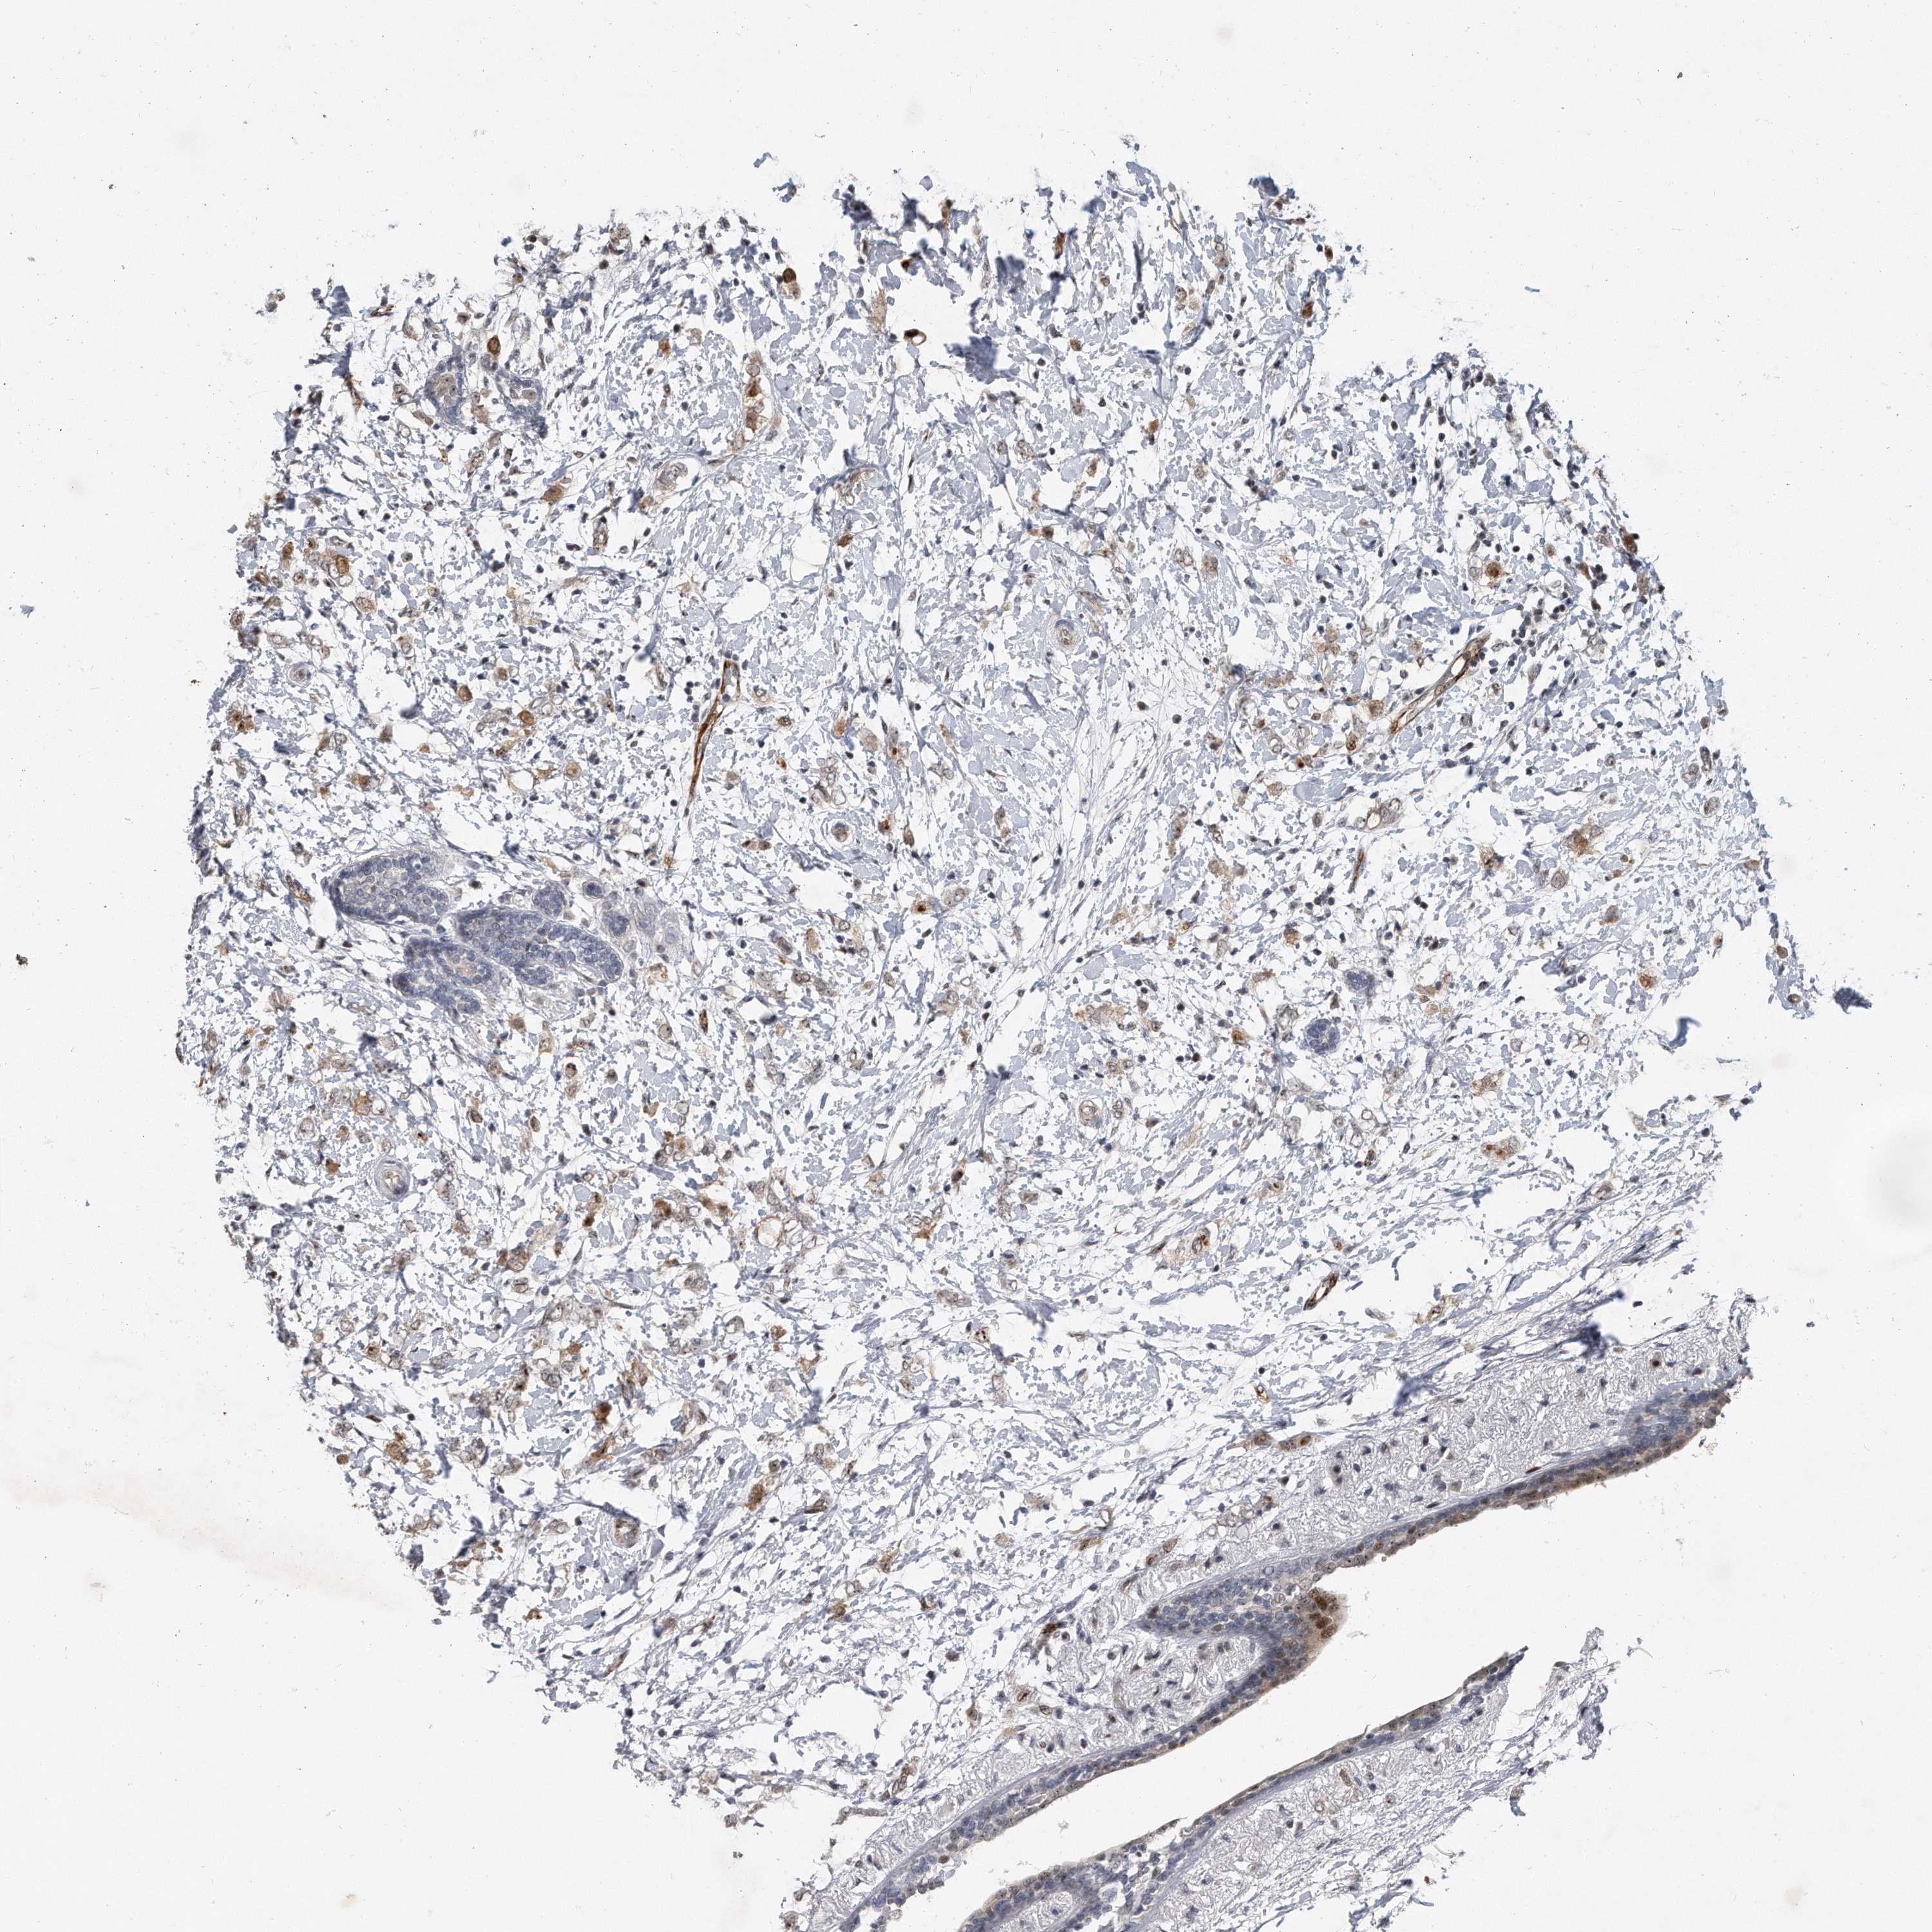

BRCA TCGA BRCA VALIDATION PROTEIN EXPRESSION

ANTIBODIES

AND

VALIDATION